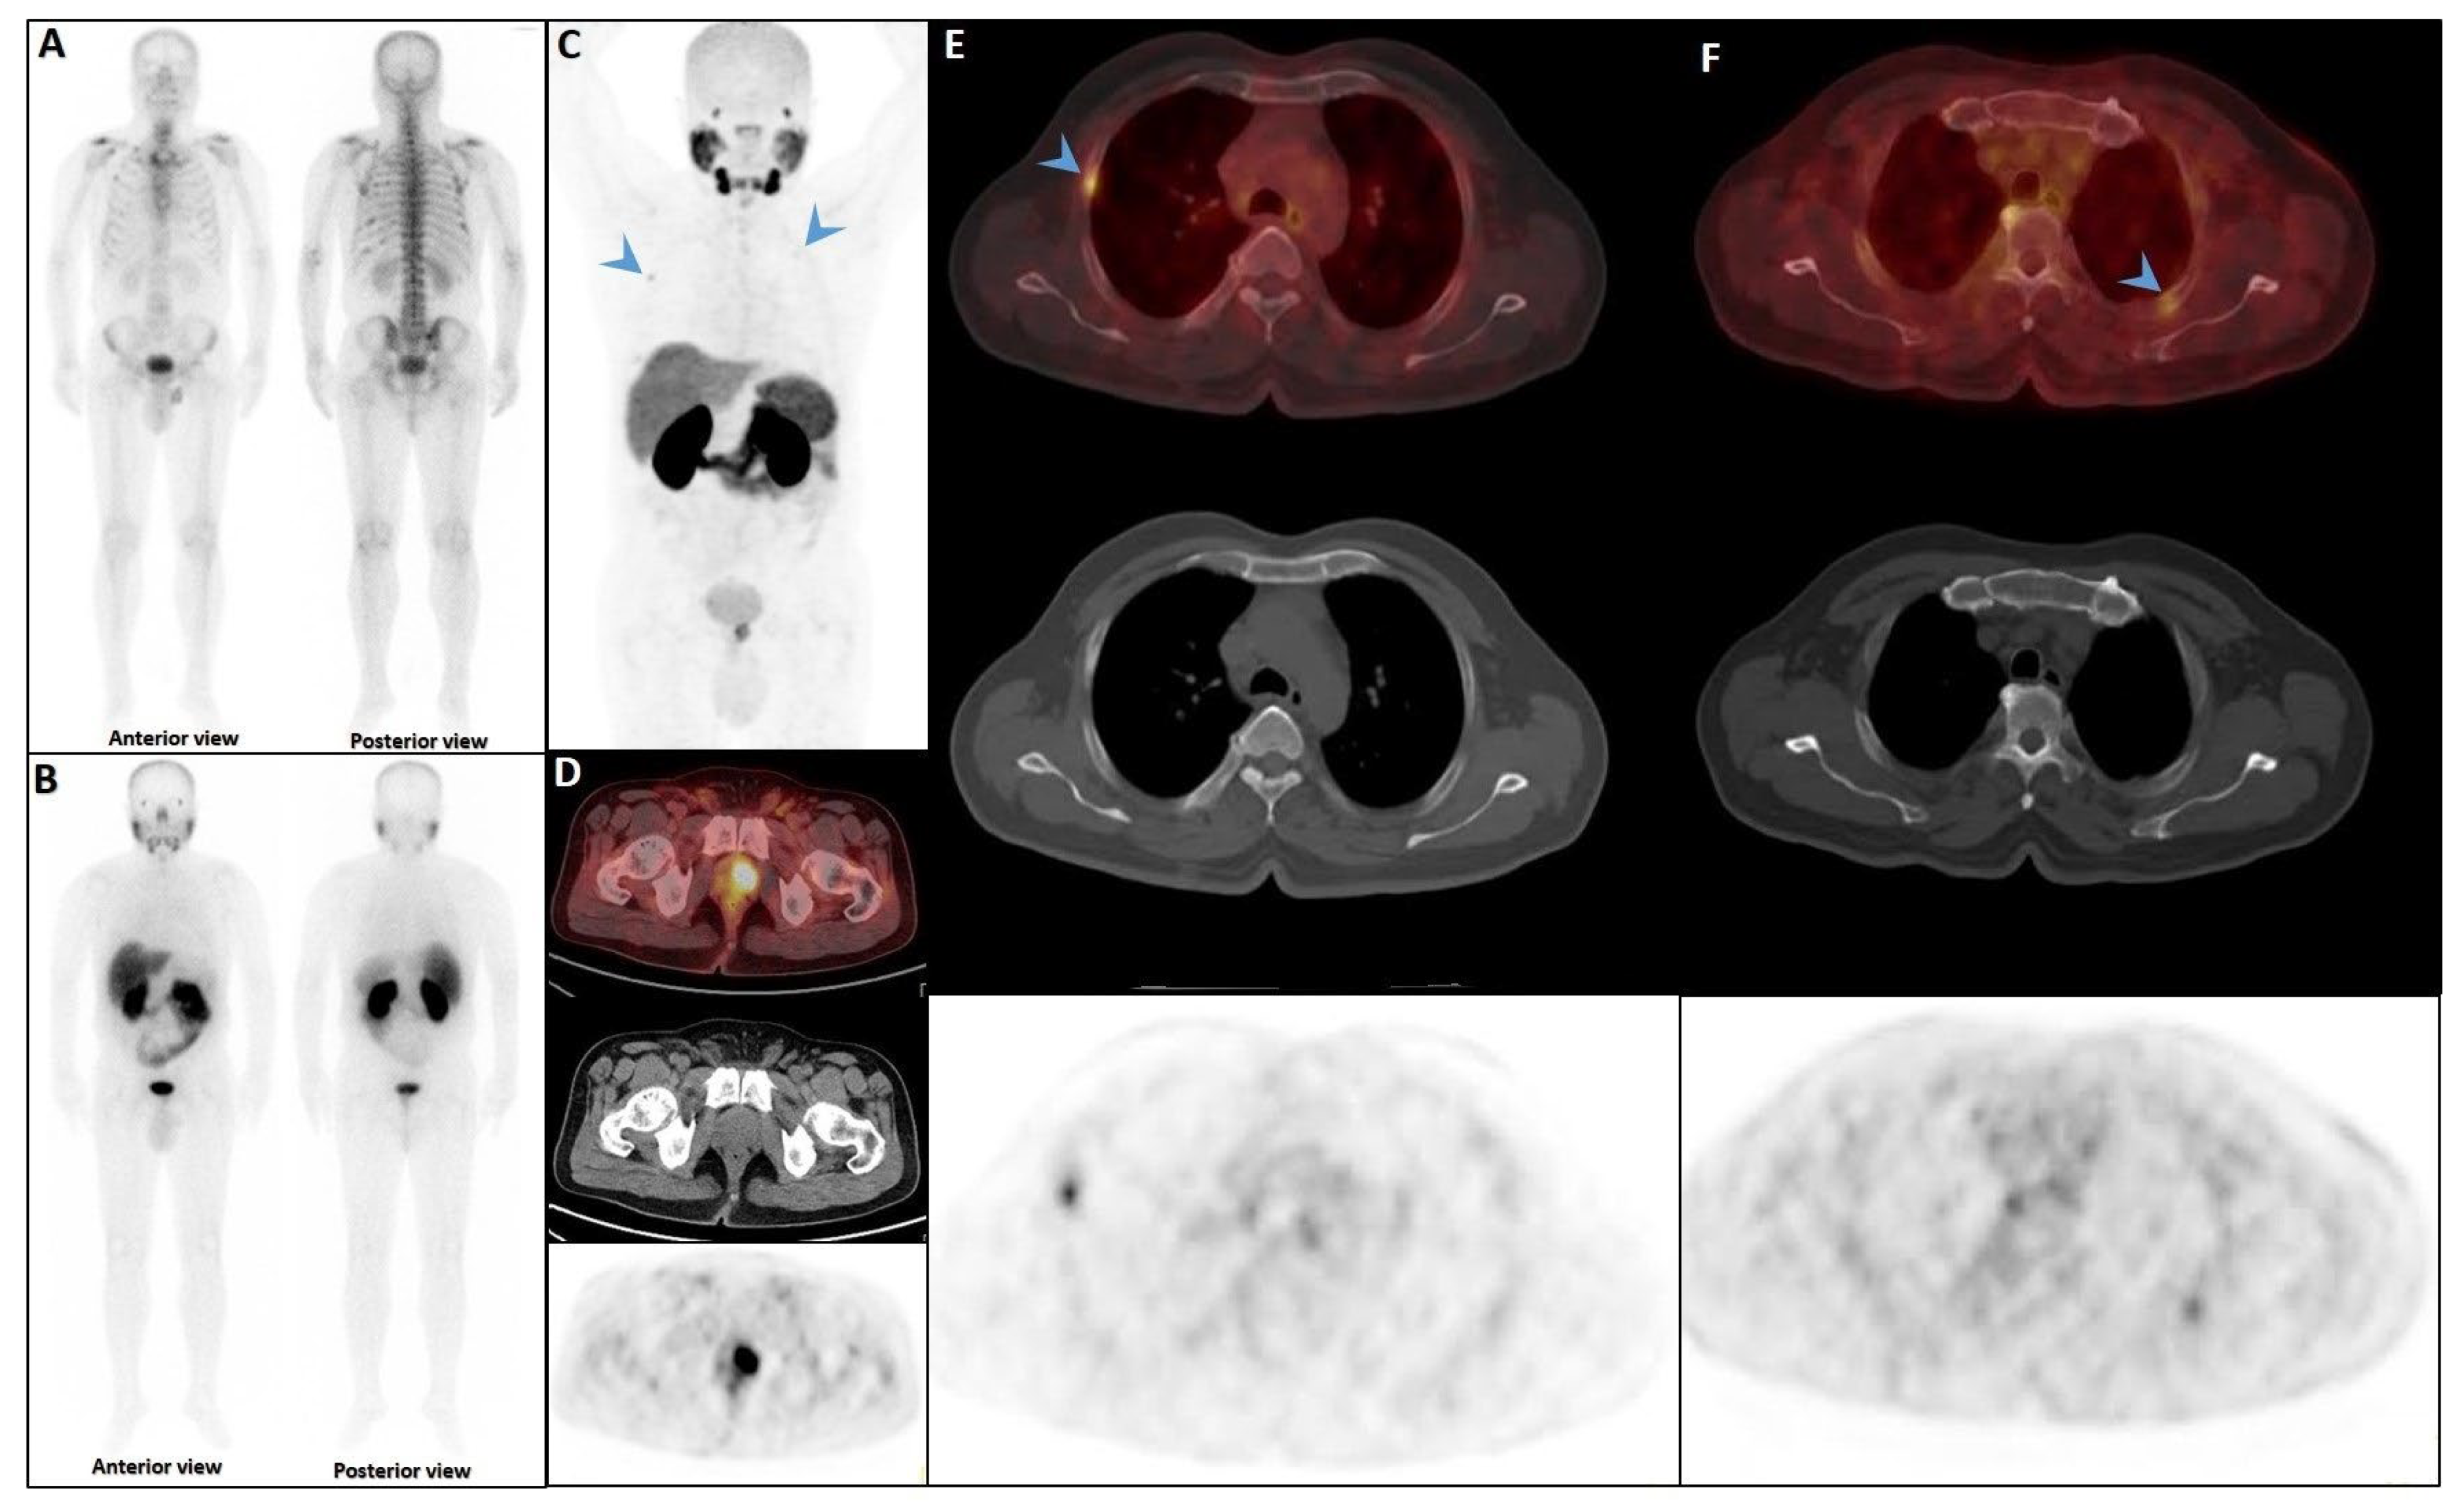

Figure 4.

Partial concordance of PSMA and bone scan. A 66-year-old man with prostate adenocarcinoma (biopsy Gleason score 4 + 5 in 8/12 cores, serum PSA = 45 ng/dL) was referred for staging. Bone scan showed four foci of increased osteoblastic activity, three in the ribs (non-consecutive, anterior/lateral aspect) on the left side as well as L5 vertebra (A). Whole-body 99mTc-PSMA scan SPECT/CT (B) showed PSMA-avid lymph node metastases in the left external iliac and left common iliac (not shown). Skeletal metastases (green arrow) in the L5 spinous process (C) and posterior aspect of the left 2nd rib (D) and lateral 5th left rib (E), and non-PSMA-avid fracture in the 4th left rib (red arrow, (F)). The patient was down-staged from polymetastatic high-volume disease to oligometastatic disease.